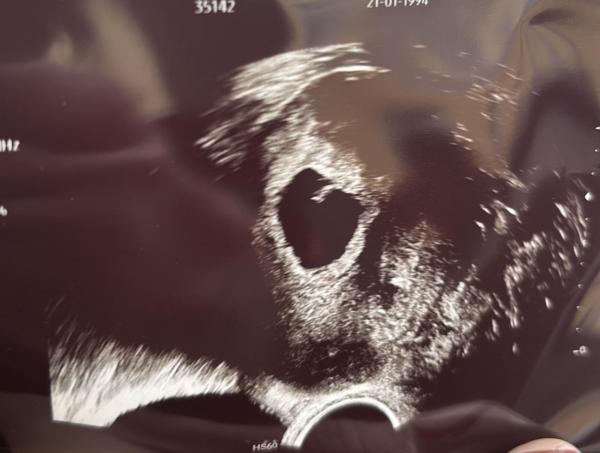

Nach 8 Jahren, 4 Fehlgeburten und einer ELSS bin ich nun wieder schwanger. Ihr könnt euch vorstellen, wie unsicher ich mich fühle!    Trotzdem möchte ich gerne einsteigen und es versuchen. Bei meinem ersten Ultraschall bei 5+4 hat die Ärztin gesagt sie sieht einen Herzschlag und einen Embryo von 3,7 mm, bei dem letzten US gestern bei 6+2 konnte leider die andere Ärztin mit ihrem schlechten US-Gerät den Herzschlag nicht finden und hat den Embryo auf 4,8 mm gemessen. Sie war aber ganz positiv gestimmt. Das macht mir jetzt alles ein bisschen Sorgen aber ich versuche, positiv zu bleiben- im besten Fall liegt es an den verschiedenen Geräten und wurde ungenau gemessen.    Wer von euch verkündet es an Weihnachten? 🎄

Bild zu Ich steige vorsichtig ein 🎄 Verkündung an Weihnachten? - Forum für August - Mamis

Ich finde man sieht es auf dem US wirklich schon gut. 🥰  Und ich weiß zB, dass meine FA mich bei meiner Eileiterschwangerschaft mit den Worten überwiesen hat, dass die im KH viel hochwertigere Geräte haben und dementsprechend auch feinere Messergebnisse bekommen können.  Da scheint es also wirklich viel an dem Gerät zu hängen. Und es scheint ja auch recht zeitgemäß gewachsen zu sein.    Wir haben es tatsächlich nach und nach geteilt. Wenn auch wirklich erstmal nur im engsten Kreis.  Mir ging es vor Weihnachten immer schon echt schlecht, weil mir so übel ist/war. Darum habe ich meine Familie dann doch schon eingeweiht, um sie nicht so sehr anflunkern zu müssen.